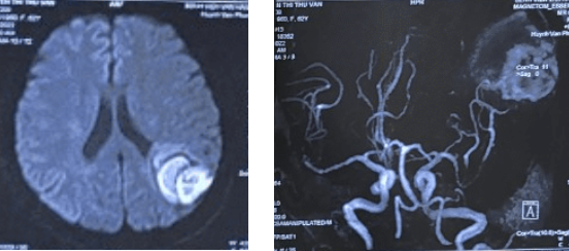

Bệnh nhân nữ 62 tuổi bị mất trí nhớ đột ngột mà không có yếu, liệt tay chân. Kết quả: Xuất huyết não đính trái giai đoạn bán cấp muộn U màng não vùng thái dương T